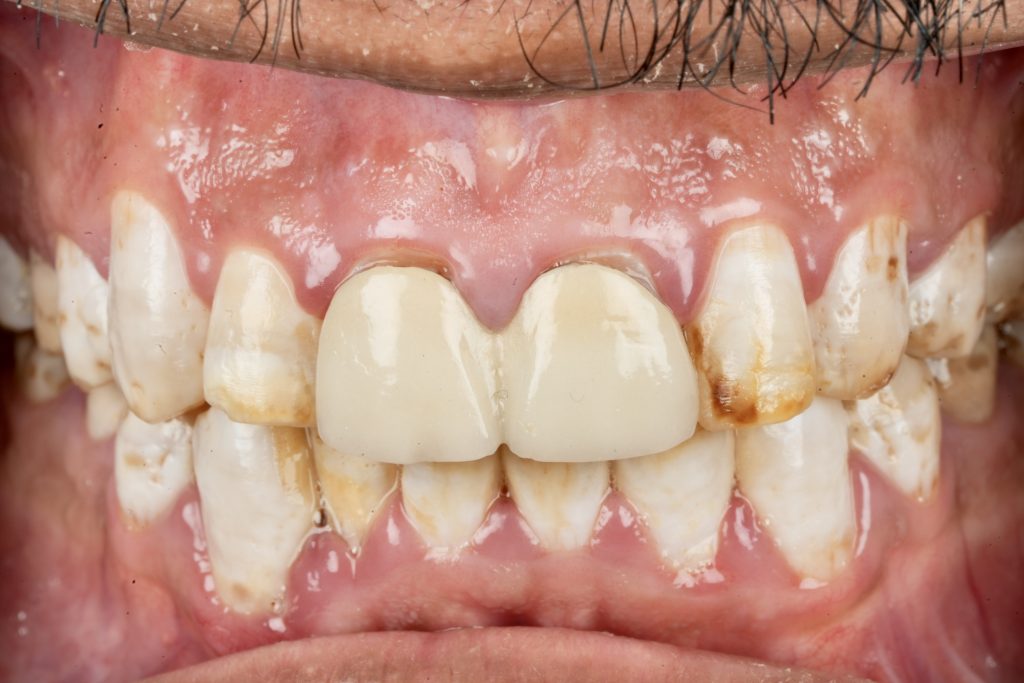

The patient sought esthetic improvement for uneven incisal edges, discolored anterior teeth, and disproportionate gingival display (Fig 1). A digital smile simulation and mock-up try-in were performed to assess tooth proportion, midline alignment, and incisal curvature. The plan prioritized enamel conservation and optical harmony.